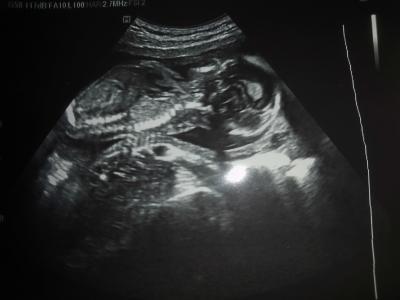

Hallo ihr Lieben, heute durfte ich endlich wieder Babygucken. Mein Mann war mit und wir wollten einen Ultraschall. Frau Dr. hat sich erst etwas geziert und meinte man würde nicht viel sehen, außer das Baby. Naja, mehr wollten wir ja auch nicht sehen... Hahaha. Also gab es einen langen Ultraschall. Alles dran, alles zeitgerecht entwickelt. Sie konnte sogar bestätigen, dass sie keinen Penis sieht, also kriegen wir wahrscheinlich eine kleine Püppi!! Mein Mann freut sich riesig und damit bestätigt sich auch die Vermutung des Arztes vom Ersttrimesterscreening. Püppi ist 221g schwer und eine Gesamtgröße von 18,2 cm. Ich bin immer noch total aus dem Häuschen, ihre kleinen Finger konnten wir sehen und auch Füßchen kam mal ins Bild. Nur der Eisenwert war mit 11,1 unter der Grenze, also bekomme ich jetzt Eisentabletten. Wünsche euch einen wunderschönen Tag, mein Grinsen wird wohl noch ein bisschen andauern... LG

Bild zu FA Besuch - Forum für April - Mamis